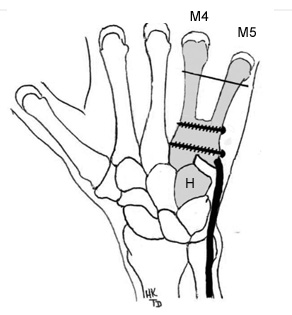

Une intervention chirurgicale est souvent nécessaire pour stabiliser la réduction par des broches.

Cette radiographie au bloc opératoire a permis de vérifier la stabilisation par 3 broches qui seront enlevées après 6 semaines.